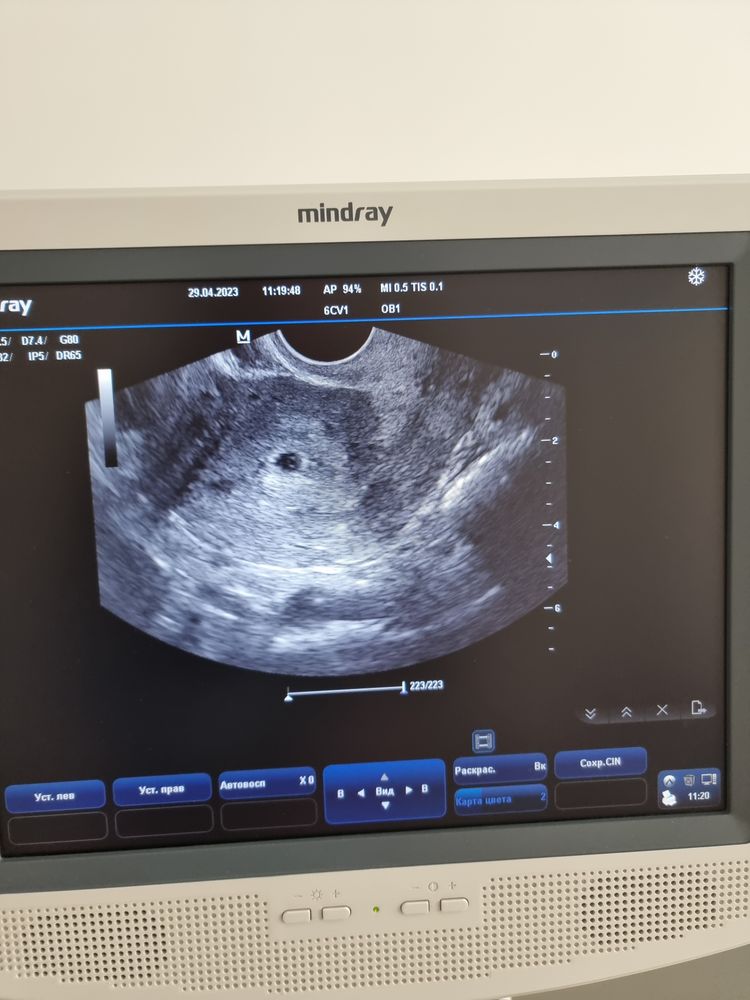

У меня перенос 13.04, узи 29.04, вот фото! Подожди программировать себя и реветь. Да, исход может быть любым, но надо попробовать поверить в хорошее. Изображение

SteLLa, просто у меня хорошего никогда не было , впервые получилось. И по этому я очень-очень переживаю за малыша 🥺 Конечно я хочу верить и надеяться на лучшее. На твоем узи видно там в плодном яйце уже что-то. А у меня ничего пока, кроме самого плодного яйца